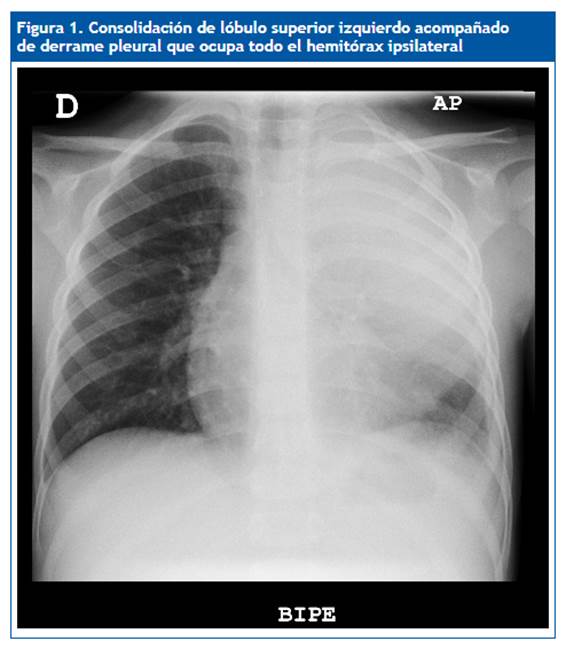

Niño de cuatro años con fiebre de siete días de evolución, diagnosticado de neumonía en el lóbulo superior izquierdo, que ingresa en el hospital con cefotaxima por vía endovenosa; tres días más tarde continua febril y presenta empeoramiento respiratorio con necesidades de oxígeno suplementario. Se realiza una nueva prueba de imagen donde se observa un derrame pleural que ocupa todo el hemitórax izquierdo, alcanzando un espesor máximo de hasta 22 mm (Fig. 1), por lo que se añade clindamicina al tratamiento y se programa drenaje con tubo de tórax. Bioquímica de líquido pleural: parámetros de exudado y antígeno de Streptococcus pneumoniae positivo. Después de diez días recibe el alta a domicilio por su mejoría progresiva, para posterior control en consultas externas.